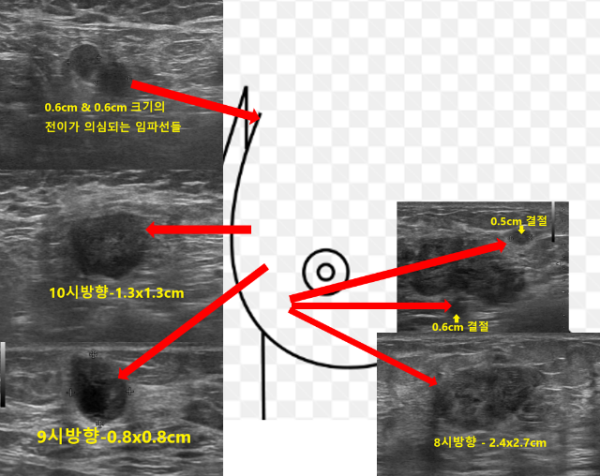

초음파 검사상 단단하게 만져졌던 오른쪽 8시방향에서 가로x세로의 길이가 약 2.4x2.7cm 크기의 불규칙한 모양과 경계를 보이는 결절이 확인되었으며 그 주위로 0.6cm, 0.5cm 결절들이 관찰되었습니다. 이뿐만아니라 그림에서처럼 9시방향 (0.8x0.8cm), 10시방향 (1.3x1.3cm)에도 악성이 강하게 의심되는 결절들이 관찰되었고 유방 촬영에서 보였던 겨드랑이에 커져있는 임파선들의 모양도 유방암의 전이가 의심되는 상황이었습니다.

이러한 소견들에 대해 충분하게 설명을 드린 후에 조직 검사를 권유하였고 내원 당일에 바로 진행하기로 하였습니다.

조직검사는 가장 유방암이 의심되는 부위인 오른쪽 8시방향 (2.4x2.7cm), 10시방향 (1.3x1.3cm), 그리고 겨드랑이 임파선, 총 3곳에서 하기로 하였습니다.